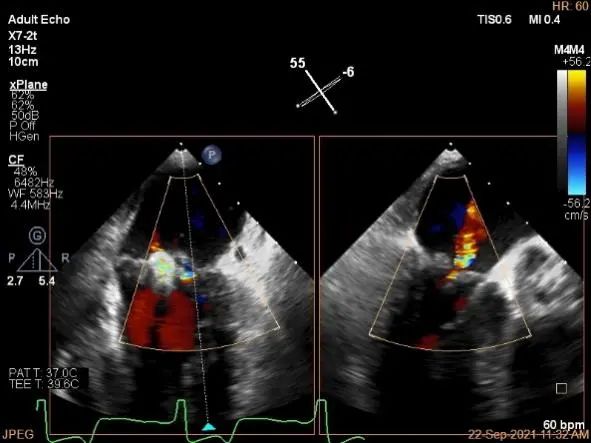

房间隔穿刺点选择

穿刺高度:4.3cm

穿刺高度:4.08cm